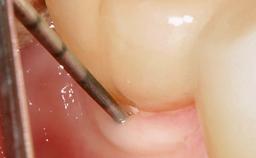

A 37-year-old male patient was referred to the Department of Periodontology at the University of Bern, Switzerland, by a private dentist. Tooth 21 had been lost due to trauma and had been replaced with an implant and a cemented single crown. The tapered-effect tissue-level implant had a diameter of 4.1 mm, a length of 12 mm, and a sandblasted and acid-etched (SLA) surface (Straumann Dental lmplant System; Institut Straumann AG, Basel, Switzerland). The metal-ceramic crown had been cemented permanently, leaving a submucosal gap between the implant shoulder and the crown margin. Absence of marginal bone loss apical to the polished transmucosal neck of the implant could be observed .